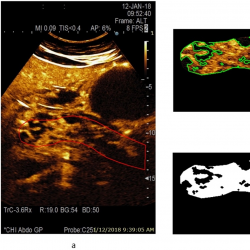

infor453_g004.jpg

Fig. 4

A CEUS image of a pancreas at 22 s after injection of contrast agent, and estimated area of a healthy parenchyma (according to the presence of perfusion) from a male patient with acute necrotizing pancreatitis: a – contrast harmonic image of the pancreas region and manually selected ROI marked with a solid red line, b – extracted informative ROI for further automatic detection of healthy parenchyma areas marked with a solid green line, c – automatically detected area of a healthy parenchyma (white colour) covering 55.6% of overall pancreas ROI.

An example of a CEUS image of a healthy pancreas (healthy female volunteer) acquired at 15 s after injection of contrast agent and an estimated area of healthy parenchyma (according to the presence of perfusion) is presented in Fig. 3. The automatically detected area of healthy parenchyma is marked in white, with the area covering 100.0% of the overall pancreas ROI. The CEUS B-mode image of pancreas affected by acute pancreatitis (male patient) acquired 22 s after injection of contrast agent, and an estimated area of healthy parenchyma (according to the presence of perfusion) is presented in Fig. 4. Here, the automatically detected area of healthy parenchyma (white) covers 55.6% of the overall ROI. The remaining part of the tissue is affected by necrosis and covers 44.4% of the overall ROI.